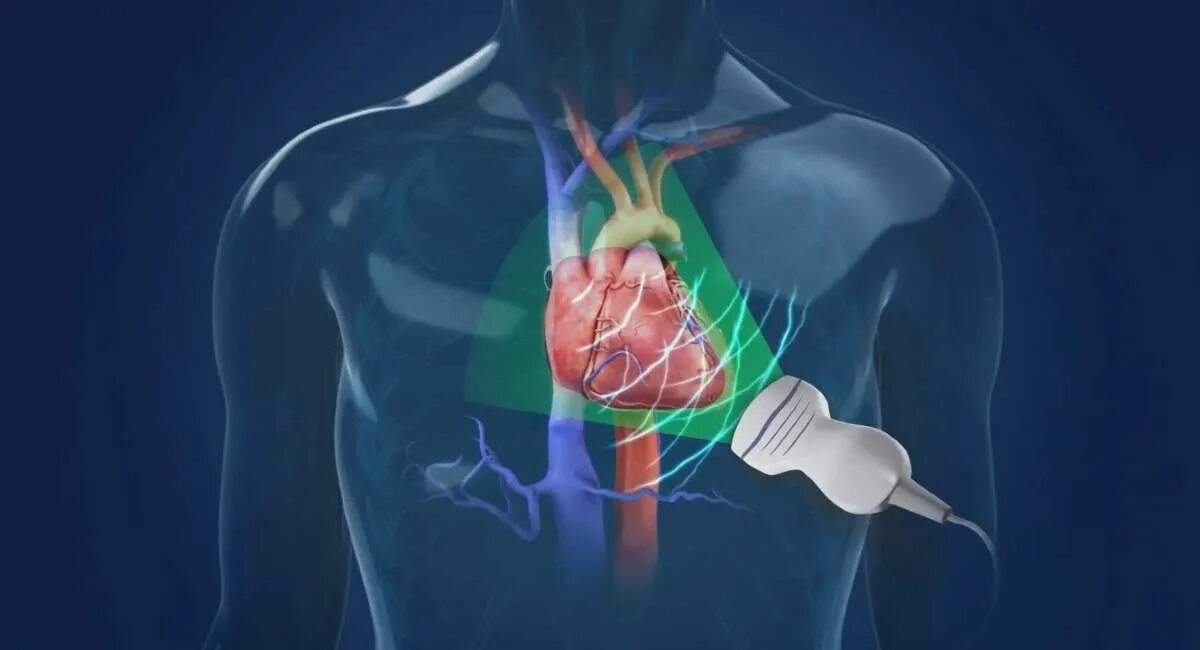

Эх сердца